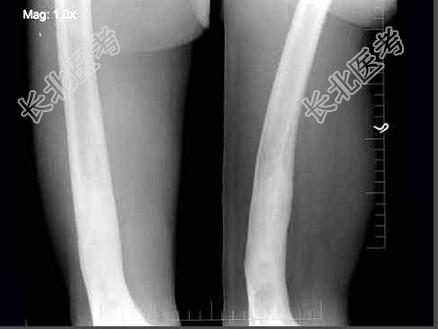

- 单项选择题男,58岁, 右大腿酸痛,弯曲变形, 有外伤史,右股骨摄片如图所示, 最可能的诊断是 ( )

A、硬化性骨纤维结构不良

B、慢性化脓性骨髓炎

C、骨质软化症

D、慢性硬化性骨髓炎

E、以上均不正确